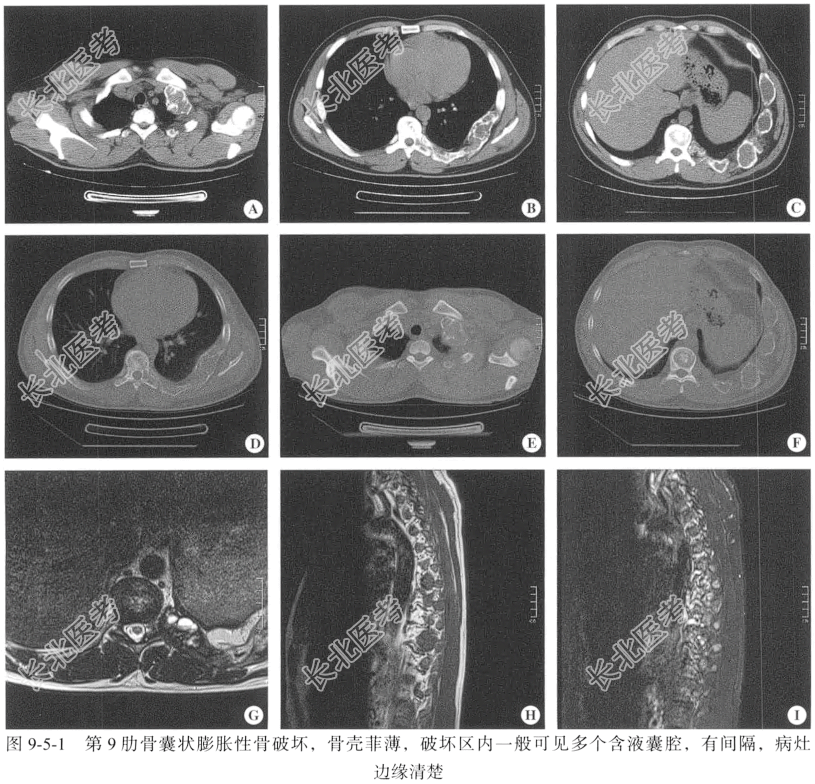

【影像图片】见图9-5-1。

【胸部CT平扫检查】仰卧位,包括骨盆轴位的骨窗、软组织窗,扫描范围从第6颈椎椎体到第12胸椎椎体水平。

【胸椎MRI检查】仰卧位,包括冠状位的T₁WI、T₂WI、T₂+STIR脂肪抑制,T₁+FS+增强,矢状位的T₂WI、T₁+增强,轴位的T₂WI、T₁+增强。扫描范围自第7颈椎椎体上缘至第1腰椎椎体下缘,扫描层后为5mm,层间隔2mm。